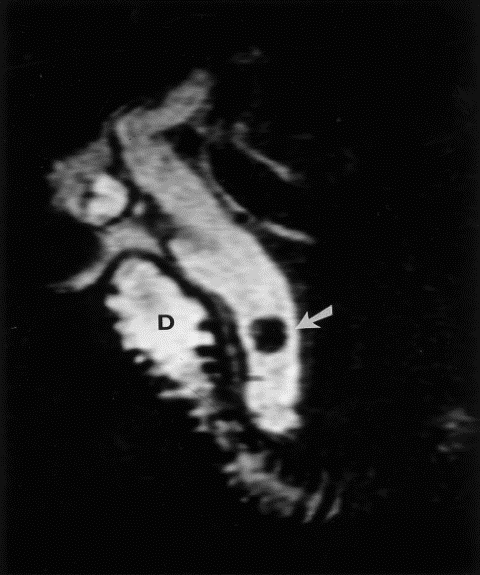

3.3.5. Chụp cộng hưởng từ mật tụy

Cộng hưởng từ mật tụy được dùng để:

- Kiểm tra các bệnh lý của gan, ống mật, túi mật, tuyến tụy như u, sỏi hay viêm nhiễm.

- Tìm nguyên nhân viêm tụy.

- Tìm nguyên nhân gây ra đau bụng.

- Sử dụng như một phương pháp chẩn đoán ít xâm lấn hơn so với nội soi đường mật ngược dòng (ERCP).

Vì vậy đây là phương pháp có giá trị chẩn đoán chính xác rất cao. Tuy nhiên có nhược điểm là chi phí tốn kém, không thực hiện được nếu có dị vật kim loại trong cơ thể.

Hình 7. Hình ảnh sỏi đường mật trên phim MRI [5]